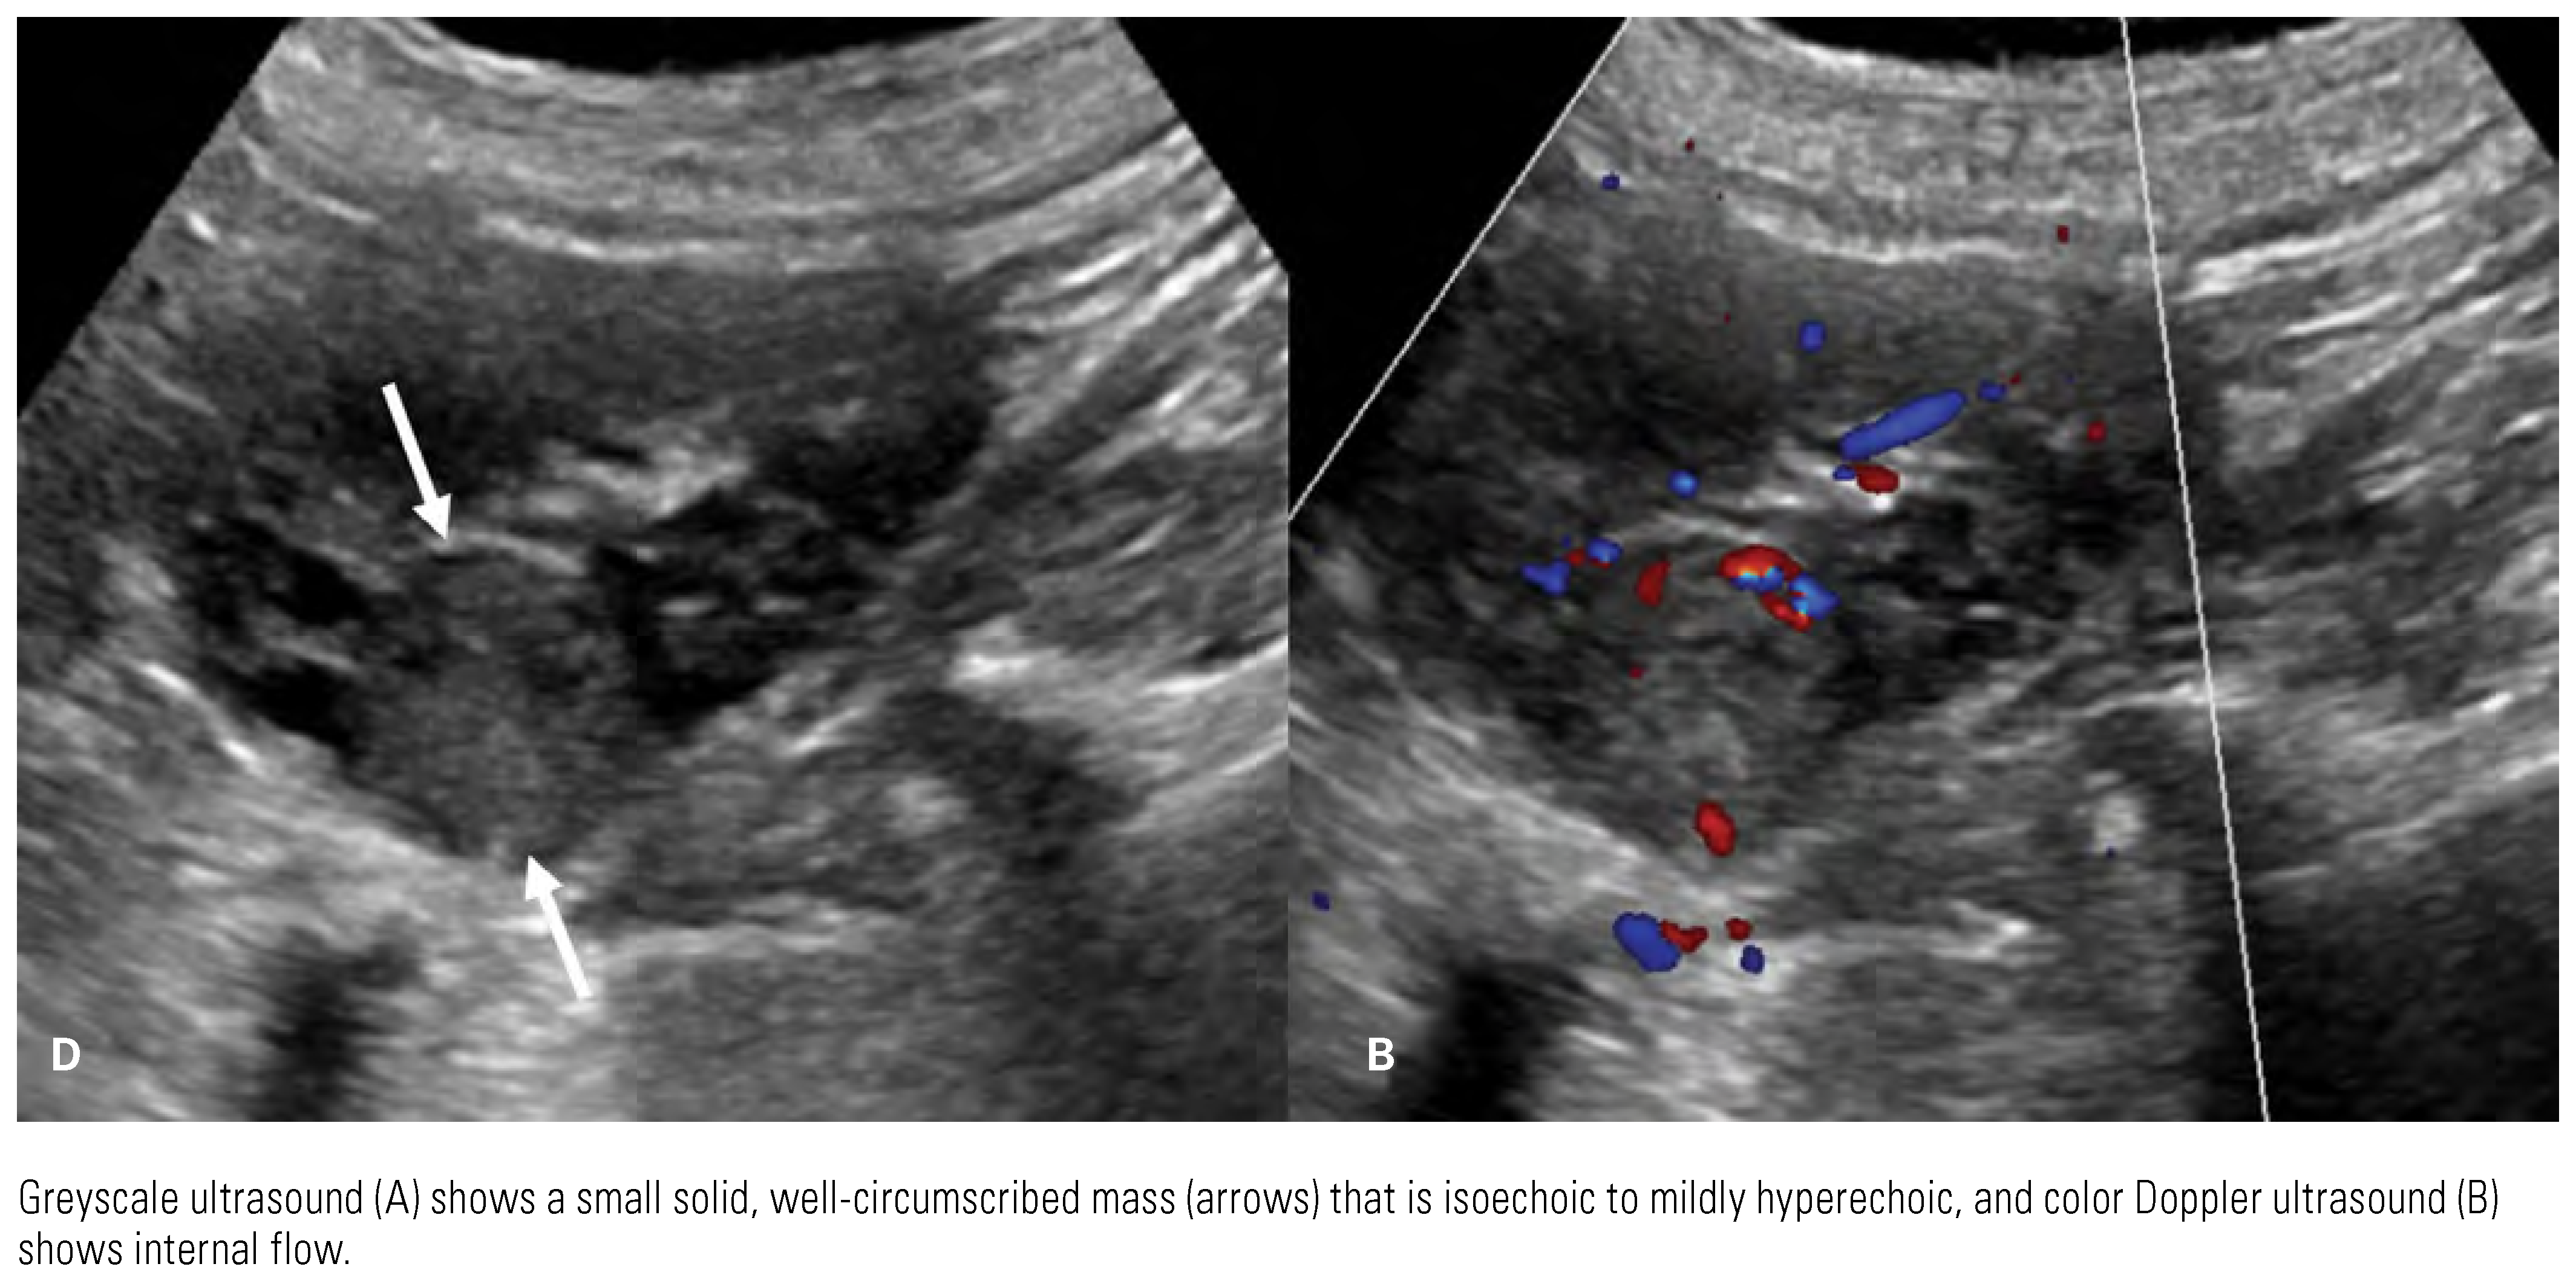

![]() |